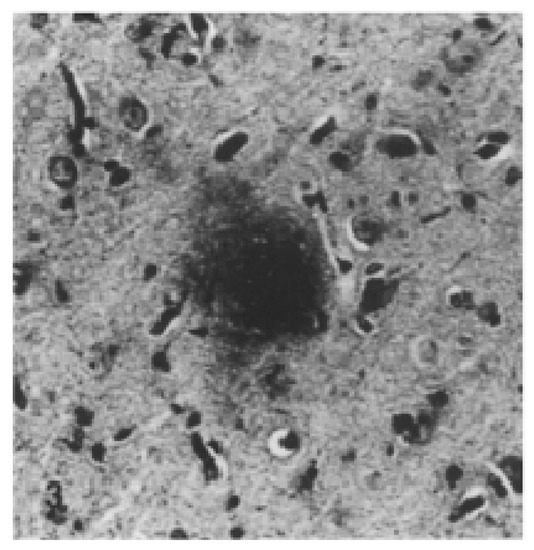

| Alzheimer’s-like disease | Domestic cat | Aβ oligomers aggregates in cats aged 8 and more Senile plaques in cats aged 10 and more NFTs only in the presence of Aβ Neuronal loss Neuronal degradation | Spatial disorientation or confusion Altered social relationships Intensified aggression or passiveness Changes in daily schedule and wake-sleep pattern Changes in interest in food Decreased grooming Inappropriate vocalization | [66,67,68,69,70,71] |

| Canine Cognitive Dysfunction (CCD) | Dog | Cortical atrophy Dysfunction in the neurotransmitter systems Increased oxidative damage Extracellular deposition of diffuse Aβ Neuronal loss Decreased neurogenesis Tau abnormalities, but not NFTs Ventricular enlargement Oligomers of Aβ in the CSF | Loss of cognition and recognition Loss of house training Disorientation Changes in their sleep-wake cycle | [74,75,76,77,78,79,80,81,82,84,85,86] |